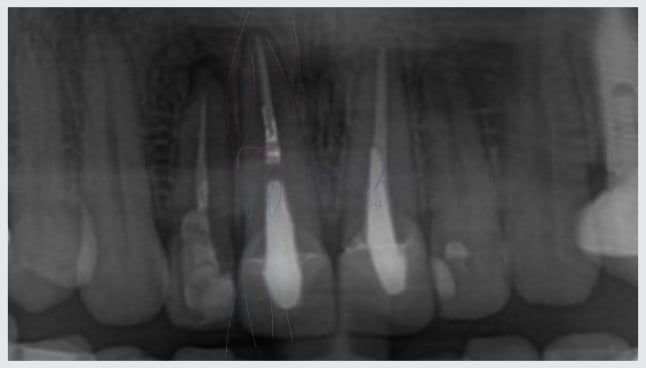

Outro motivo para retratar o canal ocorre quando em exames de Raio X surge alguma lesão ou cisto na ponta da raiz (aparece que uma imagem escura e arredondada).

Esses cistos dentários acontecem quando há bactérias infiltradas no conduto do canal, indicando que o primeiro tratamento de canal não foi bem sucedido ou foi mal executado, seja pela dificuldade anatômica do dente ou falha na obturação dos canais.

Podem portanto ter ficado restos do antigo nervo dentário da raiz ou bactérias que o infeccionavam.